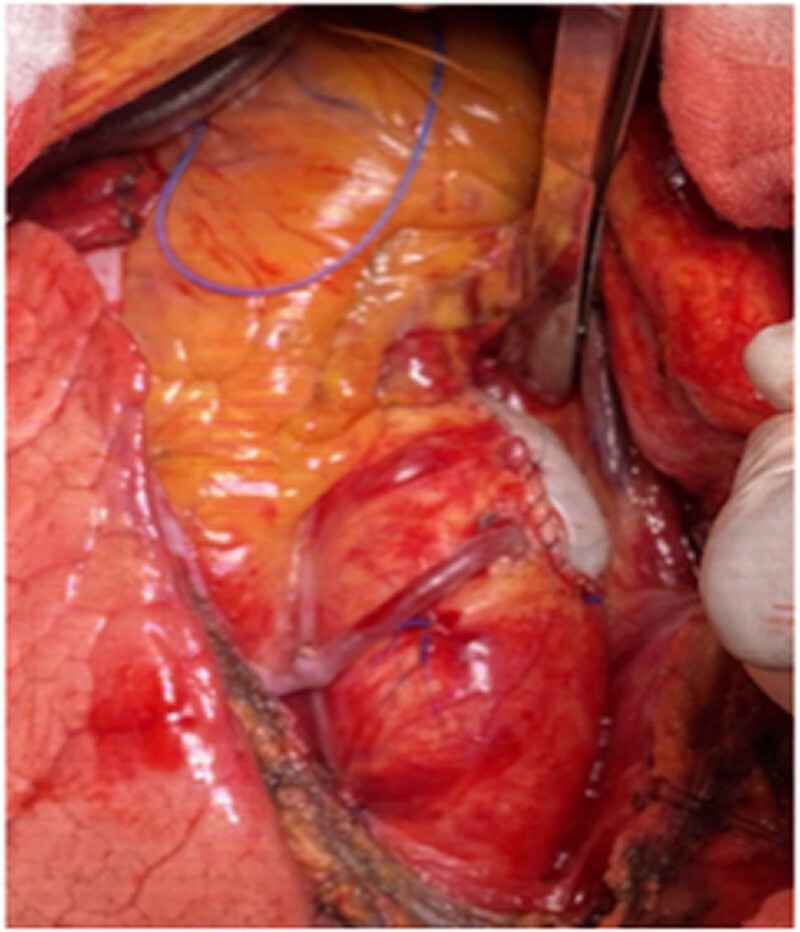

瓷主动脉不是主动脉瓣和/或冠状动脉旁路移植术的绝对禁忌症,但它需要一个特殊的策略和个体化的方法来减少栓塞并发症的风险和在打开和/或关闭主动脉切开术期间的技术问题。

Porcelain aorta is not an absolute contraindication for aortic valve and/or coronary bypass grafting but it requires a special strategy and individualized approach to minimize the risk of embolic complications and technical problems during opening and/or closing the aortotomy.